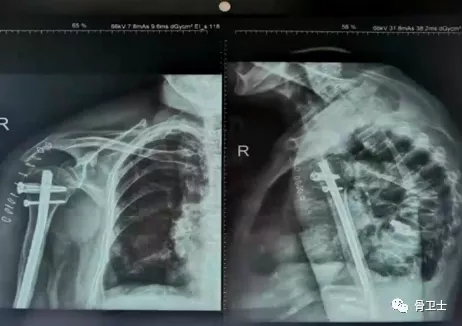

主诉:2021年5月13日因"外伤后右肩部疼痛畸形,活动受限5小时“入院治疗,既往高血压病史,未定期监测血压及口服降压药物。查体:右肩部皮肤明显肿胀,右肩部内收畸形,搭肩试验阳性,可及异常活动,右肩部活动受限,远端血运感觉可。辅助检查:血型A型,Rh(D)血型阳性。5月12日血常规示血红蛋白94g/l,电解质、肝肾功能、血糖、凝血功能、输血前四项未见明显异常。心电图未见明显异常,头颅+胸部CT示未见明显外伤性异常;右肩关节正侧位片+右肩关节三维CT:右肱骨近端骨折,老年性骨质疏松症。

▲X光片

诊断:右肱骨近端骨折(Neer分型3部分骨折);老年性骨质疏松症;轻度贫血;高血压病。治疗方法:入院后于5月14日,在全麻下行右肱骨近端骨折髓内钉内固定术。胡立冬主任指出,此患者具有手术指征,针对此类患者也有几种不同的手术方案,如钢板固定、髓内钉固定和关节置换。选择手术方式要根据患者的实际情况,因为患者有骨质疏松,如果采用钢板固定,肱骨头把持力度不够;如果采用关节置换,手术时间短,出血量大,伤口大,术后患者疼痛比较严重,置换时假体放置的时机、位置非常重要;髓内钉固定创伤小、手术时间短,更符合生物力学的要求,髓内钉系统属于轴心固定,应力遮挡效应较小,骨膜剥离少,神经血管损伤的可能性小,患者术后康复良好。